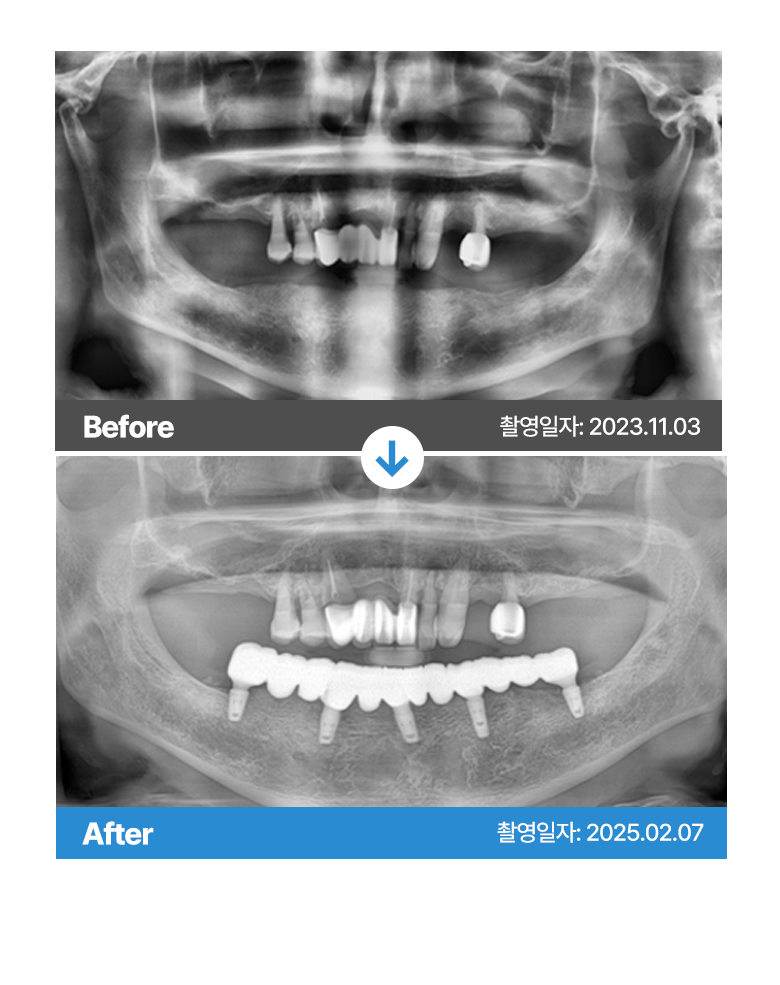

* 본원에서 치료 받으신 환자분의 사례로

환자분의 동의를 얻어 활용함을 안내드립니다.

개인에 따라 결과차이, 부작용 등이 발생할 수 있으므로

의료진과의 상담을 통해 신중히 결정하시기 바랍니다.

* 본원에서 치료 받으신 환자분의 사례로 2차적인 가공이 없으며, 환자분의 동의를 얻어 활용함을 안내드립니다.

개인에 따라 결과차이, 부작용 등이 발생할 수 있으므로 의료진과의 상담을 통해 신중히 결정하시기 바랍니다.